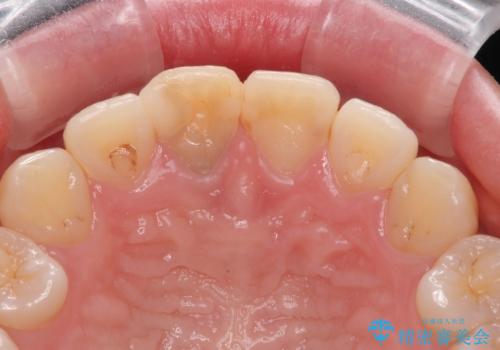

- 神経を取り除いた後に歯の色が変色して気になってきたとのことで来院された患者様です。

前歯は片側のみ神経を取り除かれていましたが、反対側もむし歯治療の詰め物が広範囲に及んでいたため、両方の歯をオールセラミッククラウンにて補綴治療を行うこととしました。

奥歯も著しく茶色に変色していたため、同様にオールセラミッククラウンにて補綴治療を行うこととしました。